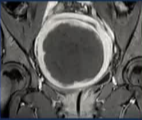

影像学检查:盆腔磁共振(MRI)平扫+增强是金标准。用于明确肌瘤的大小、数量、位置(如浆膜下、肌壁间、粘膜下)、血供情况、与内膜的关系,并排除恶性可能。这是决定治疗方案的关键

实时监控:医生通过实时影像(MR或US)规划治疗范围,逐点进行消融。治疗中医生会与患者沟通,如下腹部发热、酸胀等感觉均属正常。